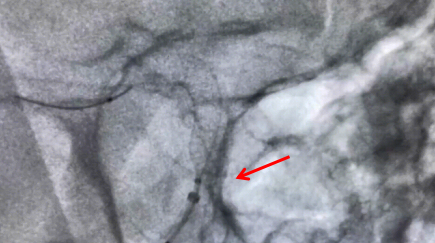

手術中釋放支架圖片

牟科杰主任醫(yī)師介紹,顱內動脈瘤是血管壁形成的囊狀突起,是顱內“不定時炸彈”,動脈瘤介入治療,已經從彈簧圈栓塞時代進展到了血流導向密網支架治療的時代。傳統的治療方法是單純彈簧圈栓塞或支架輔助彈簧圈栓塞或開顱夾閉,但對于一些瘤頸寬、瘤體大、多發(fā)動脈瘤的患者,血流導向裝置成為一種最佳的治療手段。通過血流導向密網支架的釋放,重建血管內血流方向,使動脈瘤血栓化,促進血管內皮的再生及修復,最終使瘤頸閉合而治愈。血管重建技術是顱內動脈瘤血管內治療的重大突破,它使得一些復雜的腦動脈瘤治療風險相對降低,術后復發(fā)率低,同時也讓手術時間大為縮短,為復雜動脈瘤的治療帶來了全新方法。4月19日上午,手術歷時兩小時順利完成。